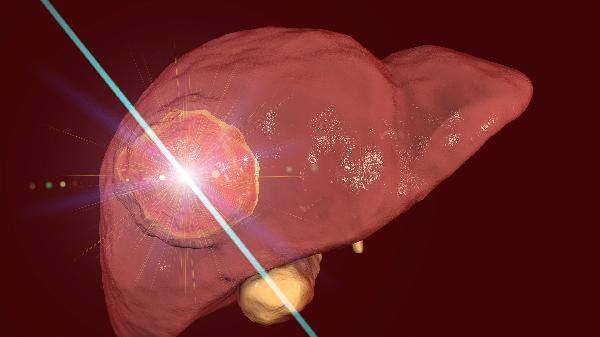

超声引导下胆囊穿刺引流术后如何护理

超声引导下胆囊穿刺引流术后护理需重点关注引流管维护、伤口管理、活动限制、饮食调整和并发症监测五个方面。